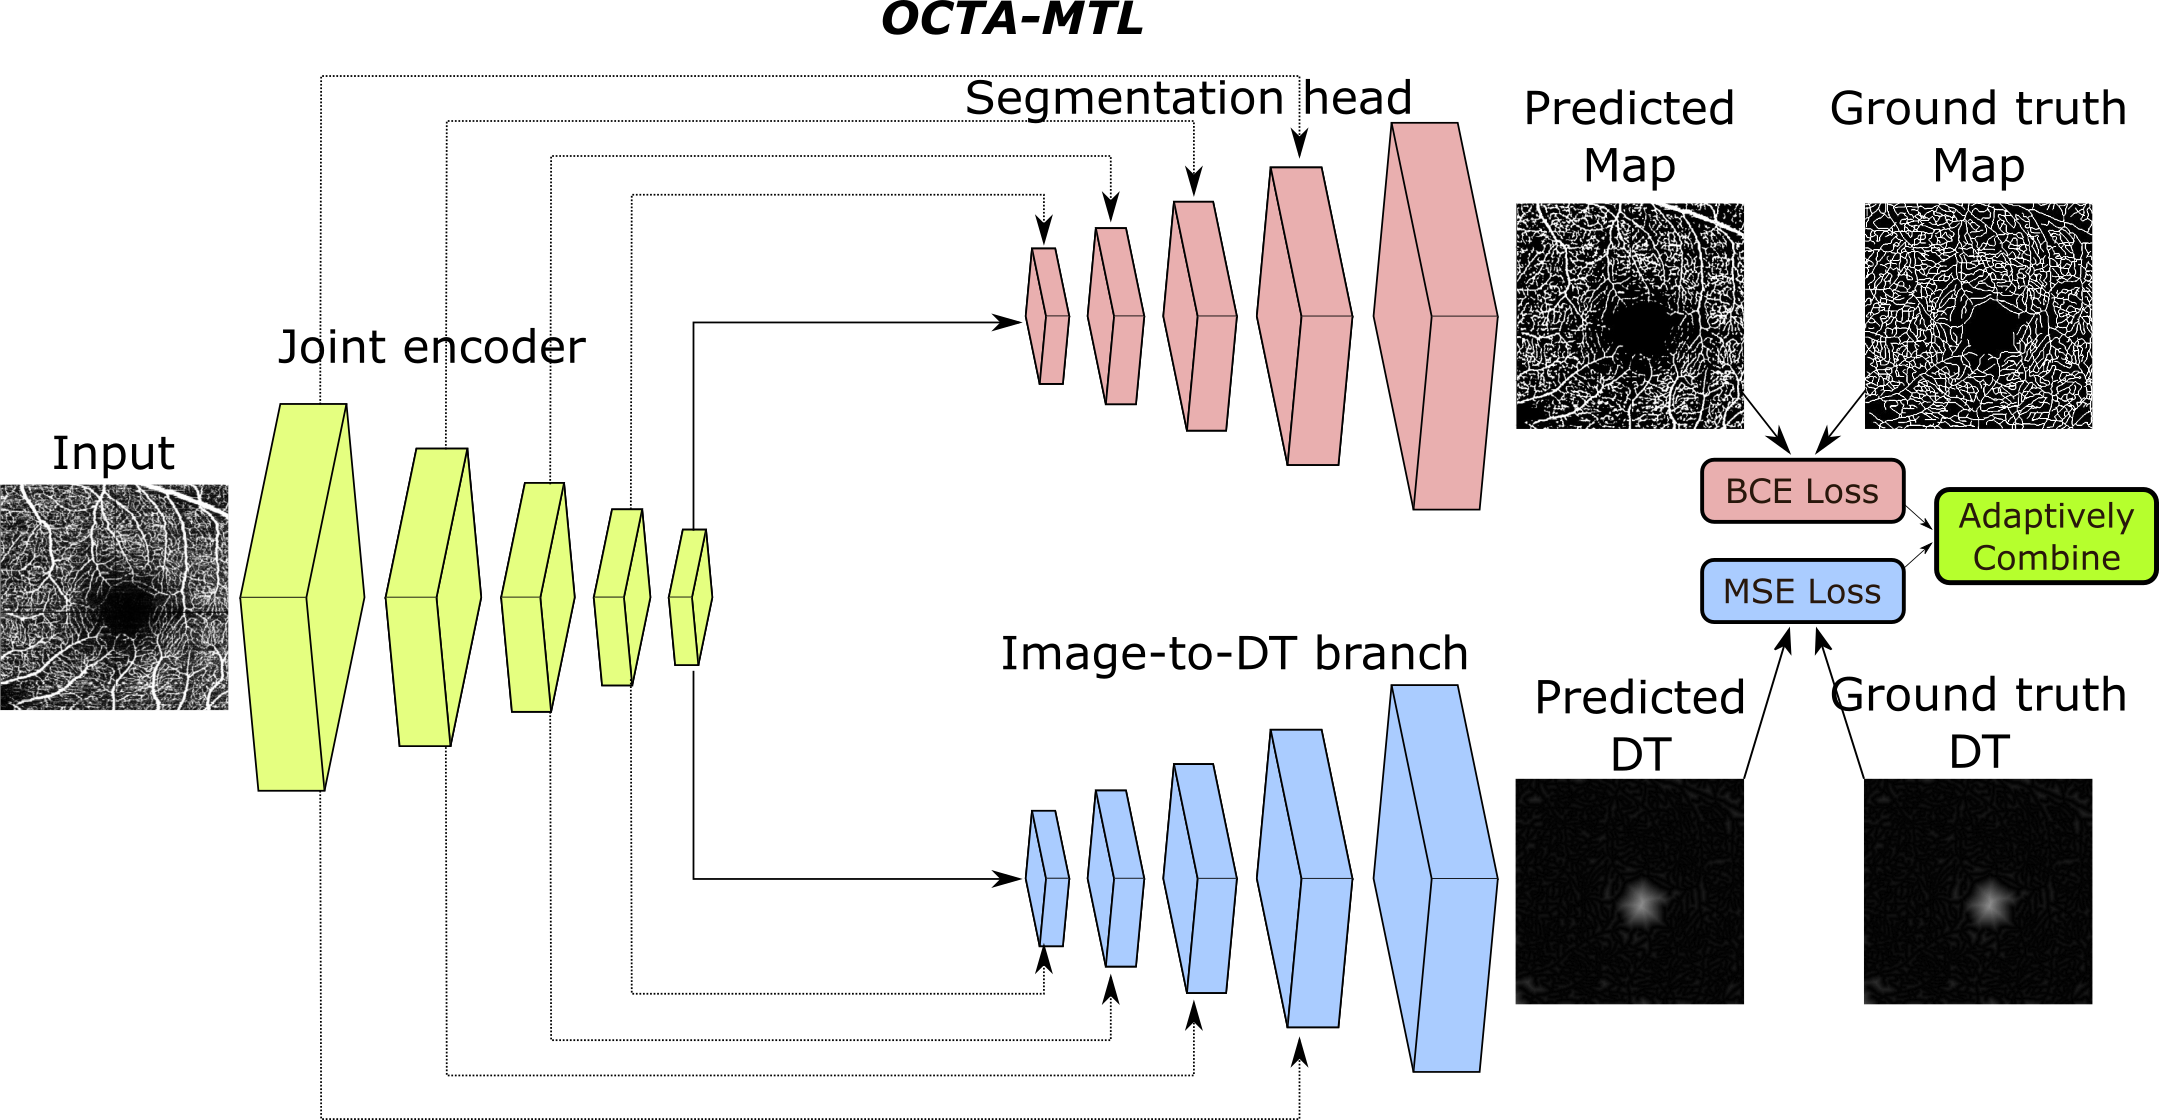

OCTA-MTL, consists of two main components: a segmentation head and an image-to-DT branch. The segmentation head is responsible for predicting the binary mask of the vessels, whereas the image-to-DT branch is responsible for predicting the distance transform (DT) of the vessels. DT is a mathematical operator that assigns to each voxel in the image the distance to the nearest vessel surface. DT can provide useful shape prior and boundary information for the segmentation task, as well as facilitate the evaluation of segmentation quality. Both the segmentation head and the image-to-DT branch share a common encoder, which extracts high-level features from the input OCTA image. The overall architecture of OCTA-MTL is illustrated in Figure 1.

Segmentation head The segmentation head of OCTA-MTL is a decoder that reconstructs the binary mask of the vessels from the encoder output. The final output of the decoder is passed through a sigmoid activation function to obtain the probability of each voxel belonging to the vessel class. Here, a binary cross-entropy (BCE) loss is calculated.

Image-to-DT branch The image-to-DT branch of OCTA-MTL is a dense-pixel regression network that predicts the DT of the vessels from the encoder output. The predicted DT is then compared with the ground truth DT, which is computed from the ground truth binary mask of the vessels using the Euclidean distance transform algorithm [12].

Adaptive loss combination To train OCTA-MTL, we use a combination of two loss functions: a binary cross-entropy (BCE) loss for the segmentation task and a mean squared error (MSE) loss for the image-to-DT task. Simply adding these two loss functions may not result in an optimal performance, as the scale and importance of each task may vary [13]. Therefore, we introduce a novel adaptive loss combination strategy that controls the relative weighting of these loss functions. Our strategy is based on the idea of dynamically adjusting the loss weights according to the inverse of the average loss values for each task. Specifically, we define a loss weight as follows:

where and are the loss values of BCE and MSE. The intuition behind this strategy is that the task with a higher average loss value should be assigned a lower weight, as it indicates that the task is more difficult or less important than the other task. By doing so, we can balance the learning process of both tasks and avoid the dominance of one task over the other. In implementation, value of is empirically estimated and updated within a batch. The final loss function for OCTA-MTL is then calculated via weighing MSE loss with and linearly combining it with BCE loss: